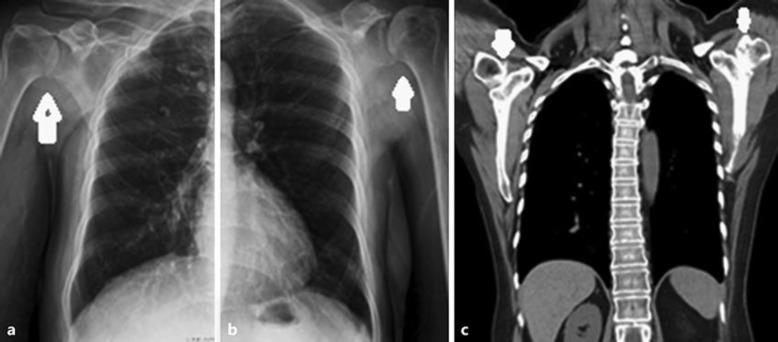

We report 2 cases of patients with solid tumors and coagulopathy who experienced avascular necrosis (AVN) of the bone following chemotherapy. Both cases exhibited nontraumatic bilateral AVN of the femoral heads, and one also showed bilateral AVN of the humeral heads. One case had multiple thromboembolic complications, including pulmonary obstructive syndrome and paraneoplastic pain. The other showed multiple paraneoplastic syndromes, with hypercalcemia and thrombocytosis. Groin pain and claudication of the lower extremities developed and persisted. Both patients eventually received bilateral hip arthroplasty due to AVN of both femoral heads.